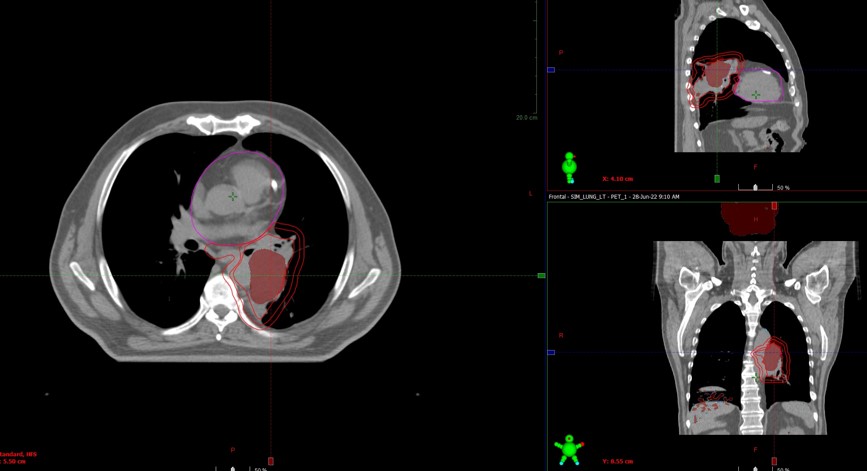

13.07.2022 выполнена КТ- топометрия органов грудной клетки с толщиной среза 2.5 мм.

Выполнено оконтуривание на КТ срезах объемов мишени (GTV,CTV,PTV) и всех органов риска

21.07.2022 был запланирован первый сеанс лечения

Пациент пришел с жалобами на выраженную одышку, кровохарканье

Во время СВСТ при первом сеансе ЛТ выявлен ателектаз левого легкого

CBCT - конусно-лучевая компьютерная томография, ЛТ – лучевая терапия